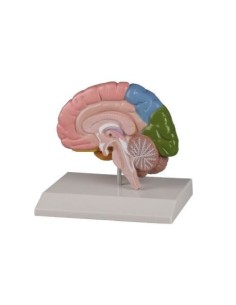

Scopri il Mondo dell’Anatomia con Modelli anatomici di Precisione

Dal cranio in 22 parti con incastri magnetici ai modelli di colonna vertebrale, da quelli di articolazioni a quelli di cuore, ogni pezzo della nostra collezione è progettato per un’immersione totale nello studio dell’anatomia umana. I nostri modelli, realizzati tramite scansioni di ossa vere, garantiscono un’esperienza tattile autentica e una fedeltà di peso quasi identica agli originali.

Essenziali per studenti e professionisti, i nostri modelli anatomici sono strumenti didattici che permettono di osservare le strutture anatomiche con precisione, eliminando la necessità di dissezioni o studi invasivi. Sono inoltre utili per spiegare ai pazienti le patologie, rendendo la comunicazione più efficace e risparmiando tempo prezioso.